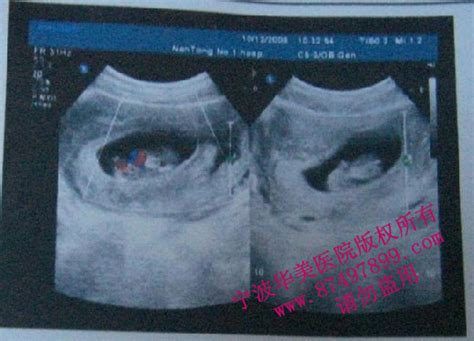

怀孕7周+5天B超单

孕囊在早期是近圆形,但在50多天时呈不规则椭圆形,因为这时胎囊内羊水张力不很大,受子宫避等限制才呈这样的,胎儿就在子宫腔的胎囊内生长发育。我们用3个值表示胎囊在近中心点位置的近椭球体的3个直径,这样3个经线相加,除以3再+30就可以大概估测孕龄,这里的径线单位是mm。